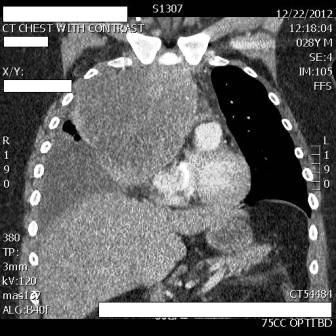

Figure 2. Coronal thoracic CT

In the ED, the patient was in acute respiratory distress and coughing violently. Initial examination revealed diminished breath sounds in the right lung field. CT scans of his chest, abdomen, and pelvis revealed a 12.9-cm right-sided anterior mediastinal mass; a large right pleural effusion; mediastinal lymphadenopathy; a small pericardial effusion; and prominent lymph nodes in the celiac, mesentery, and portocaval regions with a hypodensity in the hepatic lobe. The mass was compressing the right atrium, superior vena cava, and right lung (Figures 1 and 2). The patient was admitted to medicine.